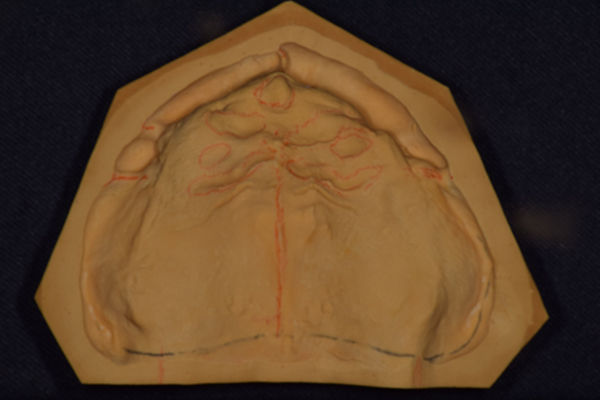

4.型取り

お口の中を診終わったら、今度は型取りを行います。まずは大まかに型取りをします。模型を作ることで、お口の中を外に出してじっくり診ることができます。歯、骨、歯ぐきの状態です。自費の入れ歯の場合、これを使って、患者さんのお口に合った型取りのトレーを作成していきます。保険の場合は作成しないこともあります。

5.精密な型取り

患者様のお口にあったトレーで、精密な型取りをしていきます。その際使用するシリコンという材料は、お口の中を精密に表現できますので、入れ歯の精度が増します。(シリコンでの印象は自費の入れ歯のみになります。)